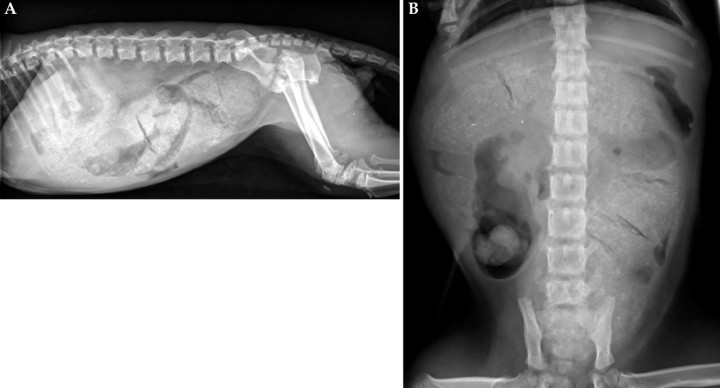

Las radiografías muestran una imagen compatible con megacolon y retención fecal grave ocupando gran parte del abdomen. Se observa retraso en el cierre de los cartílagos de crecimiento vertebrales, además las epífisis vertebrales se encuentran disminuidas de tamaño y con menor grado de osificación. Puede apreciarse disgenesia epifisaria de los cóndilos femorales y tibiales, hipoplasia de la tuberosidad tibial y de la rótula y cierre incompleto de la pelvis (Fig. 2).

<p>Mismas radiografías que en la Figura 1. Imagen compatible con megacolon y retención fecal grave ocupando gran parte del abdomen (flechas rojas). Se observa retraso en el cierre de los cartílagos de crecimiento vertebrales y las epífisis vertebrales se encuentran disminuidas de tamaño y con menor grado de osificación (flechas azules). Puede apreciarse disgenesia epifisaria de los cóndilos femorales y tibiales (flecha morada), hipoplasia de la tuberosidad tibial y de la rótula (flecha verde) y cierre incompleto de la pelvis (flecha amarilla).</p>

Mismas radiografías que en la Figura 1. Imagen compatible con megacolon y retención fecal grave ocupando gran parte del abdomen (flechas rojas). Se observa retraso en el cierre de los cartílagos de crecimiento vertebrales y las epífisis vertebrales se encuentran disminuidas de tamaño y con menor grado de osificación (flechas azules). Puede apreciarse disgenesia epifisaria de los cóndilos femorales y tibiales (flecha morada), hipoplasia de la tuberosidad tibial y de la rótula (flecha verde) y cierre incompleto de la pelvis (flecha amarilla).